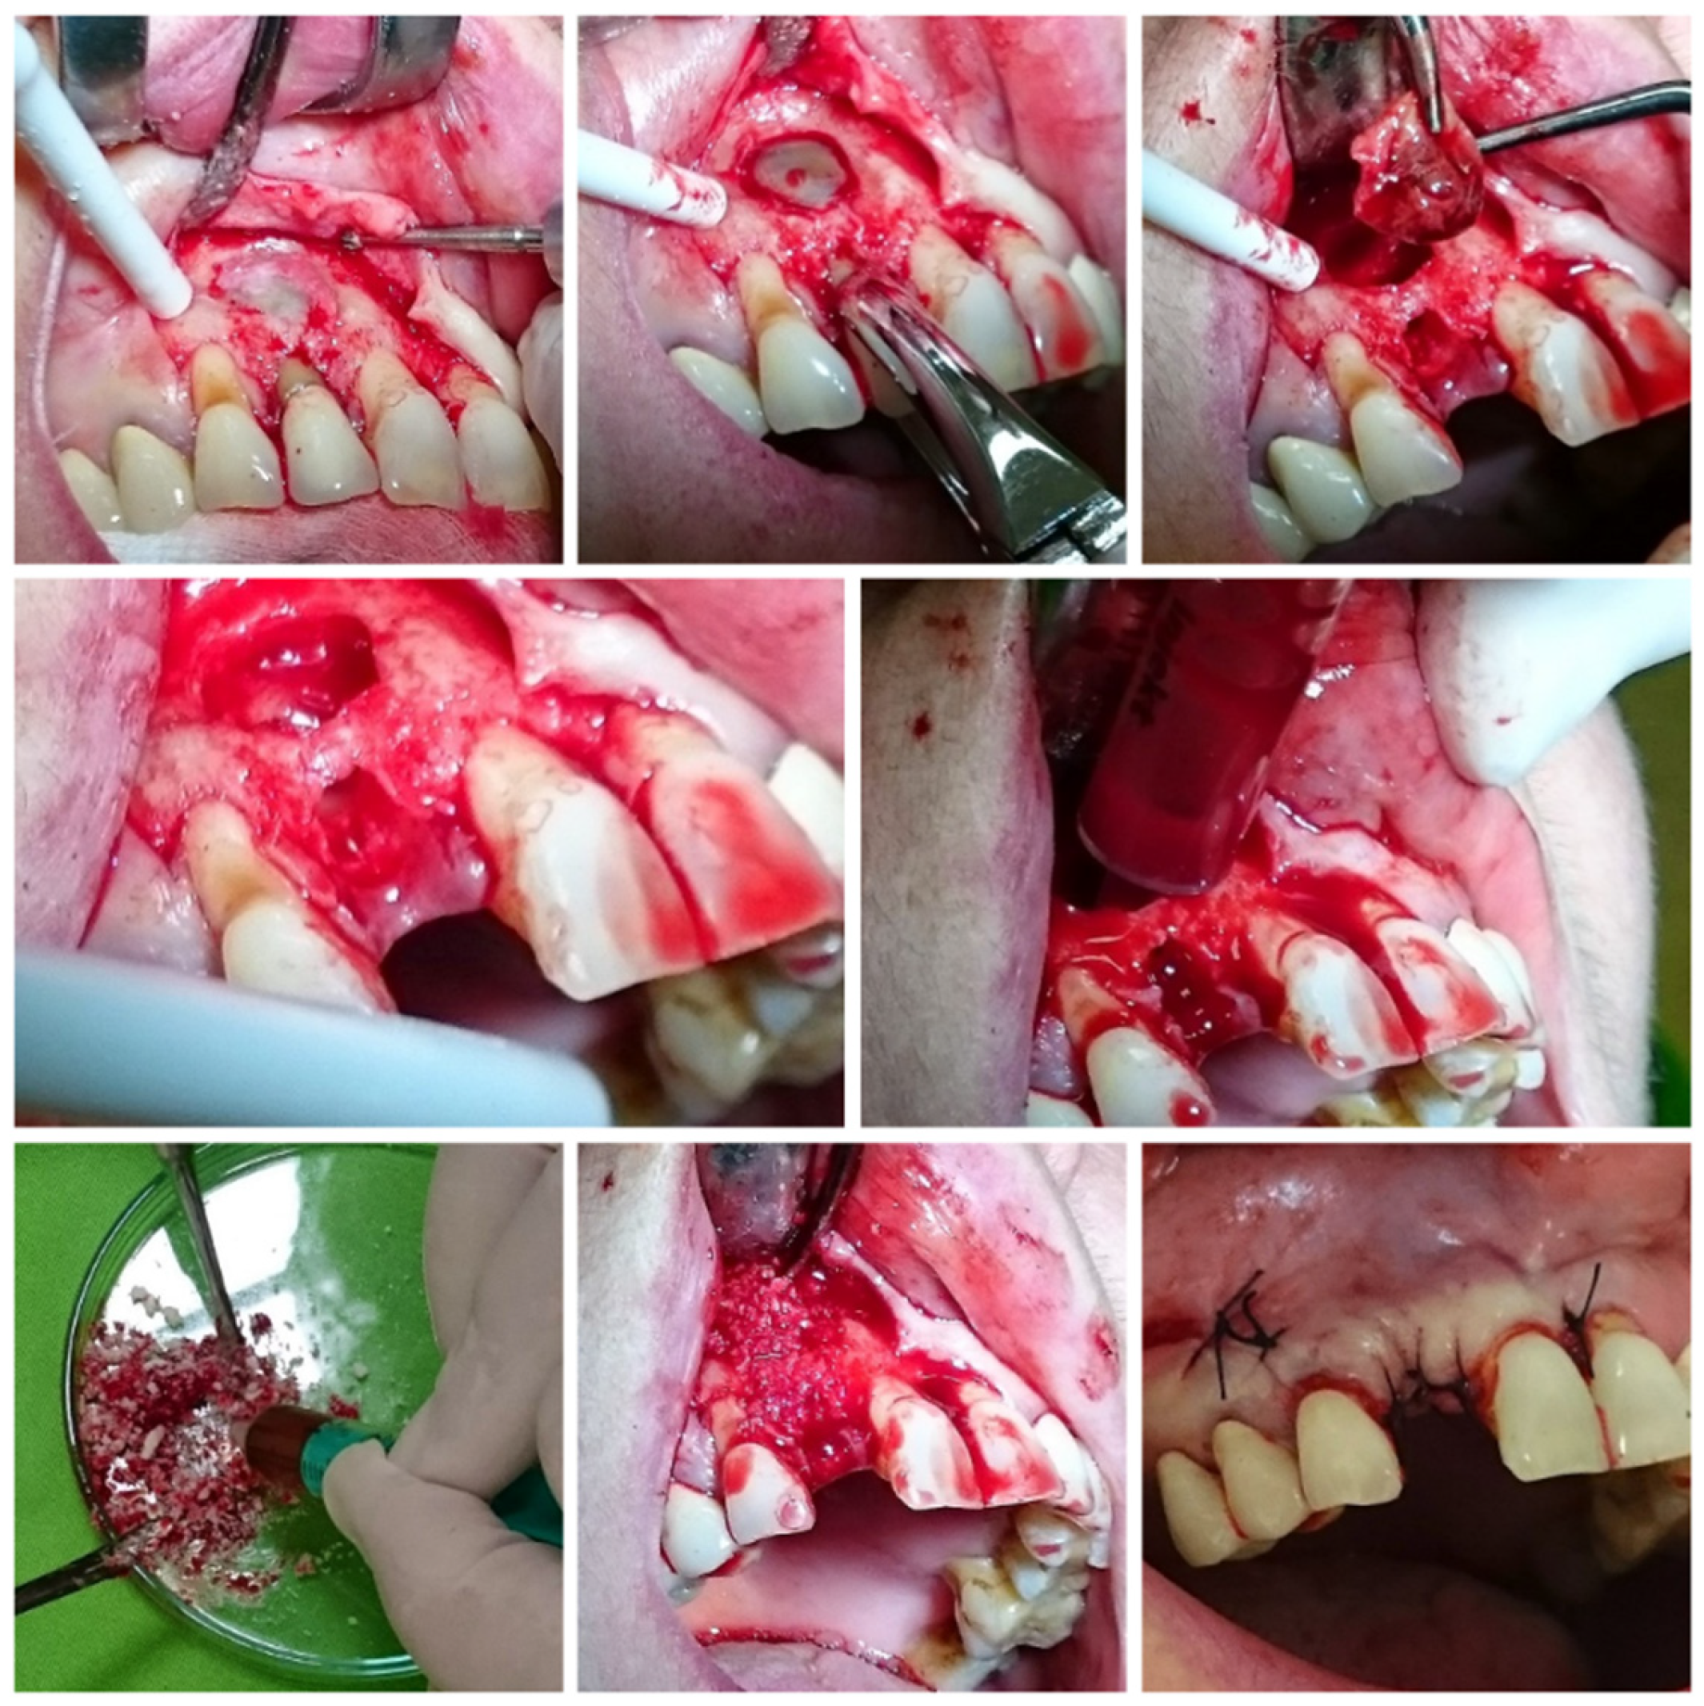

2.4. Surgical Protocol

2.5. Follow-Up